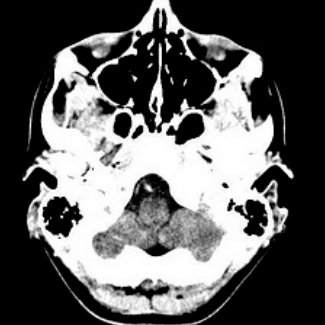

Center for Advanced Neuroimaging